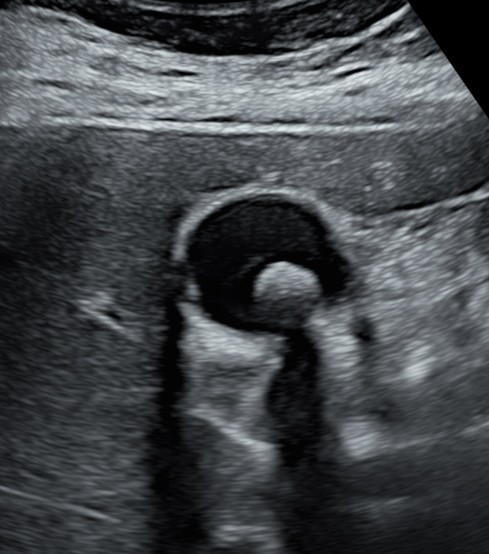

An ultrasound picture of the gallbladder with a gallstone within it.